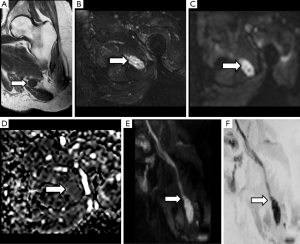

After PN trauma there is an increase of the water content at the extracellular space and a disruption of the collagen structure support. In this scenario, DWN may demonstrate thickening and focal increase of signal intensity of PN at higher b values compared with normal PN (Figure 4). ADC parametric maps demonstrate increase of ADC values reflecting the increase of water movement within the extracellular space at the site of nerve damage (36). In a similar manner, an increase of MD values will be found at the injured nerve segment. However, these parameters may appear insufficient for an adequate nerve evaluation and may not show statistically significant differences between each nerve segments. Thanks to the development of DTN sequences, diverse studies have demonstrated a decrease of FA values, due to the loss of fiber anisotropy and the presence of edema (37). At the same nerve segment, an increase of RD is depicted due to the existence of a facilitated diffusion within the perpendicular plane owing to the disruption of physiological barriers that impeded the motion of water molecules in the short PN axis, mainly myelin sheaths but also endoneurium and perineurium (38) (Figure 5). This decrease of FA values and increase of RD values becomes more conspicuous at the compression site or traction/transection point, as well as in the distal segment, probably due to a Wallerian degeneration mechanism (39). These changes are less evident at proximal segments of the damaged nerve (37). Respecting AD, it might theoretically decrease at the distal segment of a damaged PN as there is interruption of the normal axonal flow (27). However, further studies are needed to confirm or reject this assumption (Figure 6).

Brachial plexus roots and trunks on DTI after a direct or an indirect trauma demonstrate similar variations of FA or RD values to those described above for PN injuries. Neuropraxia of brachial plexus roots will show a decrease of FA values, due to loss of fiber organization, and increase of RD values (Figure 9). The amount of these changes is directly related to the severity of the neural damage and may be consider as a complementary tool to the clinical and electrophysiological evaluation (52).

Derived parameters from DWN or DTN, such as ADC or FA, have proved its usefulness to identify the involved lumbar nerve roots in cases of lumbar pain (57,58). An increase in ADC and a significant decrease in FA of compressed nerve roots compared with contralateral ones are detected in cases of symptomatic lumbar disk disease. This increase of ADC values is secondary to the venous congestion and edema that occurs in both pre-ganglionic and ganglionic segments of nerve lumbar roots (41). The decrease of FA values is also related to a loss of fiber anisotropy (Figure 11). At this point, it is important to remember that normal preganglionic nerve roots usually show physiologically lower FA values than PN, probably due to the absence of a complete neural fiber structure. This data has to be taken into account when quantification is performed at this small nerve structure, avoiding false positive results in patients without nerve compression. This quantitative assessment shows potential to form part shortly of the clinical lumbar spine MRI protocols as a tool to detect functional changes within the lumbar roots in patients with symptoms but without obvious disc protrusions (41).

The decrease of FA values has demonstrated to be more sensitive to changes in median nerve than ADC, especially at the distal carpus, after its path under the flexor retinaculum, where the most significant variation with regard to healthy volunteers is detected (63) (Figure 12). Other parameters such as MD, RD and AD have also been tested with promising results for carpal tunnel syndrome evaluation and with proper correlation with electrophysiological studies (5). Several cut-off points for FA values have been proposed for carpal tunnel syndrome diagnosis (65). However, differences due to technical factors such as acquisition protocols, magnet field strength (1.5 vs. 3.0 T), threshold FA values, reconstruction algorithms and even patient’s age can act as potential bias and limit reproducibility (66). So, until a greater degree of standardization is achieved and based on the existing scientific literature, it seems reasonable to perform measures of the different parameters at least within carpal tunnel as well as at its proximal and distal segments.